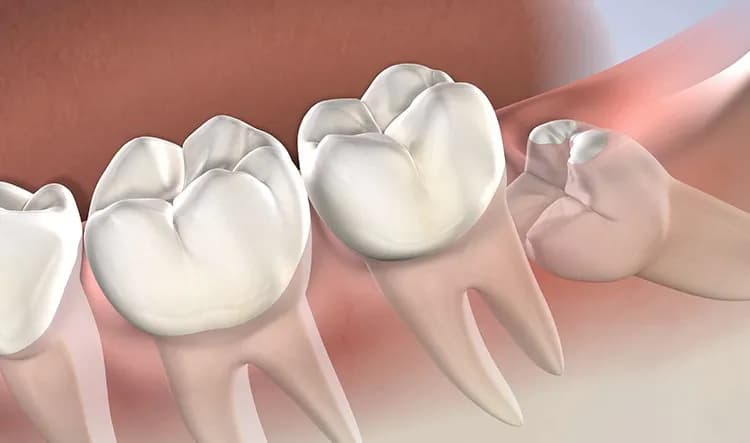

Conoce qué medicamentos se recetan después de una extracción dental para controlar el dolor y prevenir infecciones, asegurando una recuperación efectiva.